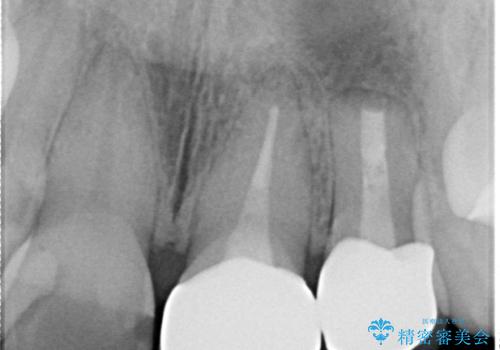

両歯とも根尖部付近を歯肉から触れると痛みを感じており、3次元CTを撮影したところ、前から2番目の歯の根尖部に病変があることが分かりました。

以前歯根端切除術を受けているものの、現在の主流とは異なる術式で行われているため、再度歯根端切除術を行うこととしました。

歯根端切除から2週間を経過した時点で痛みは全くなくなっており、処置から6ヶ月後に撮影したレントゲン写真では炎症で吸収していた骨が回復している様子が確認されました。